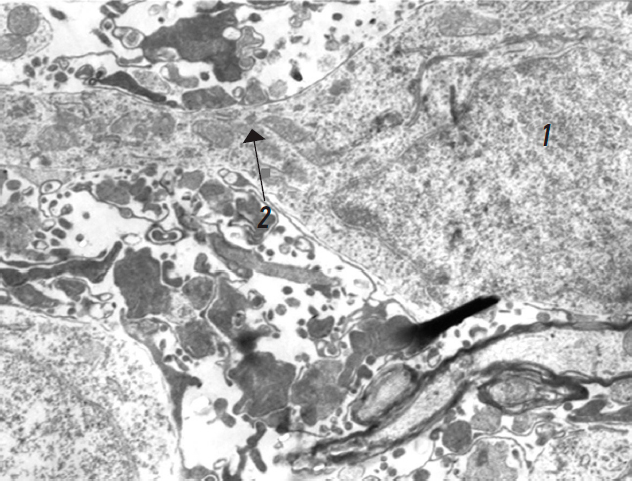

In the control group, the lumbar segment of the spinal cord predominantly contained hyperchromic neurons, characterized by densely structured nuclei and cytoplasm. These neurons exhibited a greater number of mitochondria; however, many exhibited indistinct structural features, suggesting low activity (Fig. 1). The surrounding myelinated and unmyelinated fibers were markedly altered.

Fig. 1. Hyperchromic neuron rat spinal cord without treatment: 1 — nucleus; 2 — mitochondria (arrow), ×8,300.

Рис. 1. Гиперхромный нейрон спинного мозга крысы без лечения: 1 — ядро; 2 — митохондрии (стрелка), ×8 300.

A small number of normochromic neurons were also observed. These had pale nuclei with diffuse chromatin distribution and, occasionally, dense, inactive nucleoli. Their cytoplasm contained dilated cisternae of the rough endoplasmic reticulum (RER) and, in some instances, dense lipid inclusions. Numerous ribosomes surrounded the nucleus, and a majority of the mitochondria exhibited a normal matrix and cristae structure.

These findings indicate the morphological and functional reactivity of the neurons. The axonal cylinders and myelin sheaths of the adjacent nerve fibers exhibited moderate alterations (Fig. 2).

Fig. 2. Normochromic neuron rat spinal cord without treatment: 1 — nucleus; 2 — myelin fiber, ×5,000.

Рис. 2. Нормохромный нейрон спинного мозга крысы без лечения: 1 — ядро; 2 — миелиновое волокно, ×5 000.